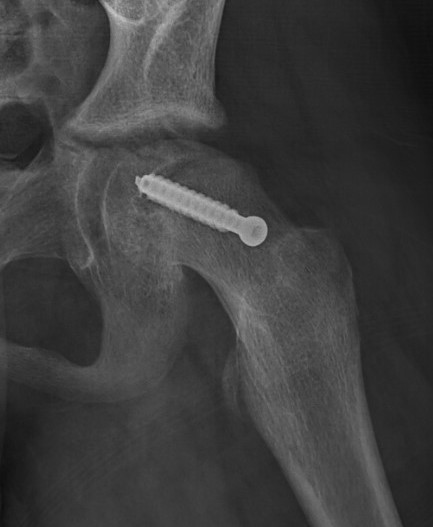

Fixation failure

![]() |